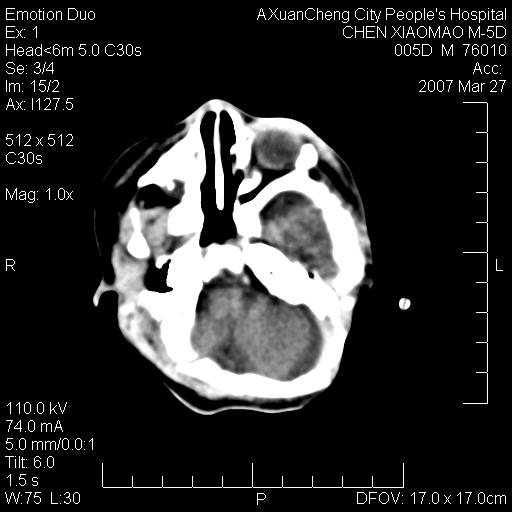

大家看看可有出血?另外枕骨中央是骨缝还是骨折

缝是正常的,但患儿有hie

大家看看可有hie ?还有左侧枕部胡形高密度ct为45~53hu,可有硬膜下血肿?

左颞枕部有出血,枕骨有骨折